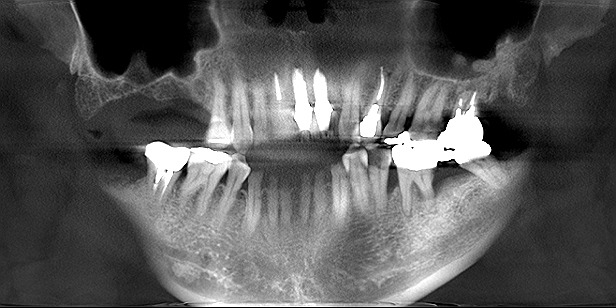

前歯部のインプラント治療 重度の歯周病が進んだ結果のインプラント治療|お知らせ |広島市安佐南区の歯科医院 前歯部のインプラント治療 重度の歯周病が進んだ結果のインプラント治療 トップ お知らせ・ブログ お知らせ 前歯部のインプラント治療 重度の歯周病が進んだ結果のインプラント治療 前歯部のインプラント治療 重度の歯周病が進んだ結果のインプラント治療 術前になります 前歯部も動揺にてフレアーアウトしています 前歯部は動揺歯のため抜歯と固定のために仮歯にしています 抜歯後4か月になります インプラント埋入時になります シェード合わせを行っています 術前術後のパノラマになります 動揺歯の固定のためクラウンへ置き換えています Web診療予約 初めての方へ 選ばれ続ける理由 院内設備について 歯が痛いしみる一般歯科 歯がぐらぐらする歯周病 健康な歯を保ちたい予防歯科 子供の虫歯予防をしたい小児歯科 銀歯をセラミックに審美歯科 白い歯を目指しませんか?ホワイトニング 矯正専門医がいるので安心矯正歯科 抜けた歯を補いたいインプラント・入れ歯 医院案内 スタッフ紹介 メリィハウス歯科クリニックオフィシャルホームページ ラベンダー歯科クリニックオフィシャルホームページ お知らせ・ブログ ホーム 診療科目 一般歯科 歯周病治療 予防治療 小児歯科 審美治療 ホワイトニング 矯正歯科 入れ歯・インプラント マウスピース矯正 初めての方へ 院長・スタッフ 設備紹介 医院案内・アクセス メニューを閉じる